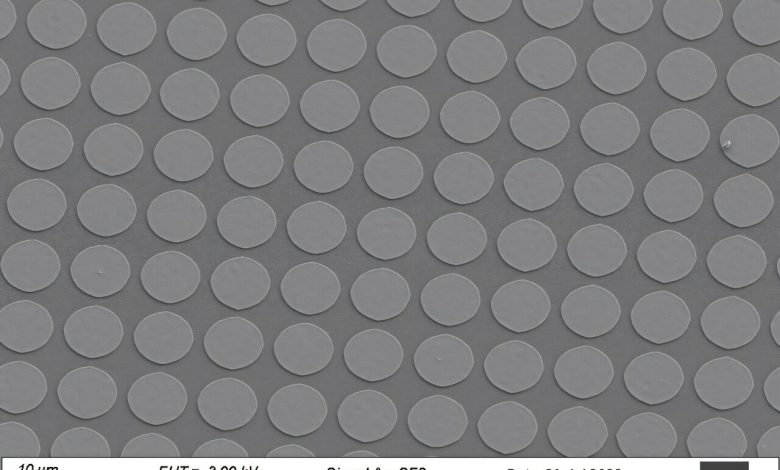

A equipe trabalha em circulatrônica há mais de seis anos. Os dispositivos eletrônicos, cada um com cerca de um bilionésimo do comprimento de um grão de arroz, são compostos de camadas de polímeros semicondutores orgânicos imprensadas entre camadas metálicas para criar uma heteroestrutura eletrônica.

Eles são fabricados usando processos compatíveis com CMOS nas instalações do MIT.nano e, em seguida, integrados a células vivas para criar híbridos de célula-eletrônica. Para fazer isso, os pesquisadores retiram os dispositivos do wafer de silício em que são fabricados, para que flutuem livremente em uma solução.